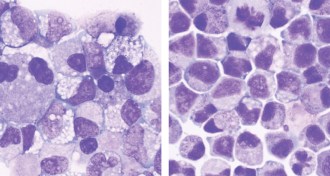

LifeMolecule boosts numbers of stem cells in umbilical cord blood

A new molecule multiplies stem cells in umbilical cord blood. More blood-making stem cells could mean more effective transplants for people with blood cancers.